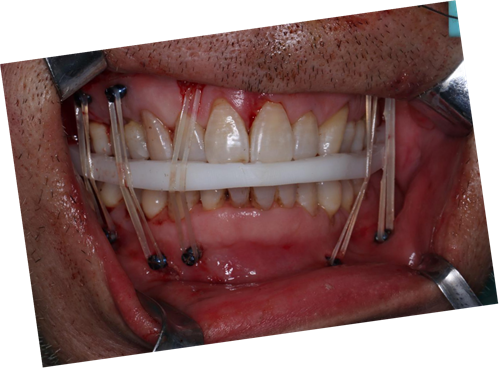

完善术前检查后,口腔科团队依据术前规划设计的方案,在导板的精确序列引导下,为患者实施了“双侧上颌骨及颧骨、右侧颧弓及鼻骨骨折切开复位内固定术、骨折颌间固定术、咬合重建术”。术后,患者骨折断端复位固定效果可靠,咬合关系恢复良好,面部基本对称,手术成效较为理想。

术中咬合板就位